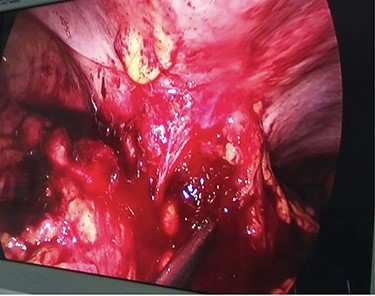

During laparoscopy, a right-sided colonic mass adherent to the lateral abdominal wall with infiltration of the subcutaneous tissue by the tumor was noted (Fig. 3).

Diagnostic laparoscopy showing ascending colon adherent to anterior abdominal wall.